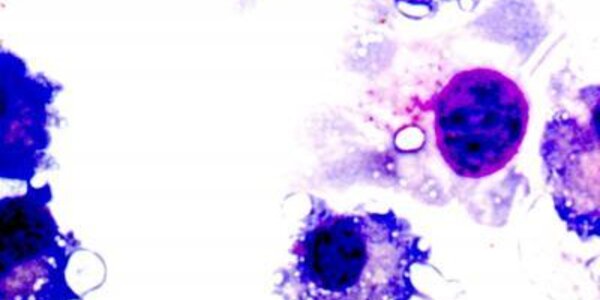

Article teaser image